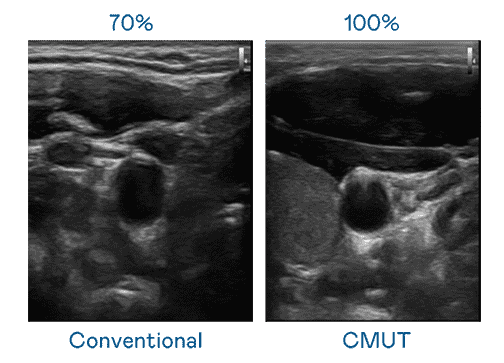

CMUT 技术是一种用电容式微机电元件来产生超音波讯号的技术。。。与传统 PZT 压电式技术相比,,CMUT 频宽增加 30%,,,,更宽频的超音波讯号让影像解析度大幅提升,,是实现高影像品质医疗超音波扫描、、、、促进精准医疗发展的关键技术。。。。

大频宽带来超清晰影像

超音波影像的解析度高低,,,首先取决于探头能发出的讯号频宽。。。人生就是博 CMUT 可提供高清晰的超音波讯号,,,提供高频宽、、、高灵敏度、、、、影像纹理细节更高的超音波影像,,协助医护人员缩短影像判读时间及利用精准的医疗影像进行诊断。。